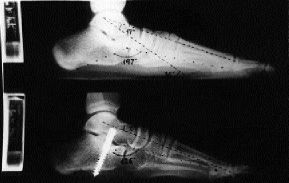

Este procedimiento se basa en la comprensión de la biomecánica del retropié, en la que se interrelacionan como diversos componentes de un mismo movimiento, tanto la flexión plantar, la adducción y la listesis anterior del astrágalo, así como la eversión del calcáneo.19 Todos ellos concurren a nivel de la articulación subastragalina de tal modo que si se frena uno se frenan todos (stop one, stop all).17 En la técnica de calcáneo-stop el tornillo colocado en el margen externo del seno del tarso, apoyándose contra la cara lateral del cuello del astrágalo justo anterior a la apófisis astragalina externa, se opone a la caída plantar, listesis con rotación interna del astrágalo e inclinación valguizante del calcáneo (Fig. 1). La corrección del antepié y arco interno serían secundarias al restablecimiento de la relación astrágalo-calcáneo. Esta corrección mantenida se estabiliza y mejora por la remodelación residual y el retensado espontáneo de las estructuras capsuloligamentosas.1

Figura 1. A: Esquema mostrando las acciones: antilistesis anterior-caída plantar del astrágalo (1), oposición a la inclinación valguizante del calcáneo (2) y a la rotación interna-caída plantar del astrágalo sobre el eje imaginario (3). Radiografías pre y postoperatorias de un niño de 13 años. En proyección AP (B) los ángulos astrágalo-calcáneo y astrágalo-escafoideo pasaron de 19 a 16° y de 59 a 66°, respectivamente. En proyección lateral (C) los ángulos astrágalo-metatarsiano, Costa-Bartani y flexión plantar del astrágalo pasaron de 17 a 0°, de 147 a 136° y de 36 a 22°, respectivamente.